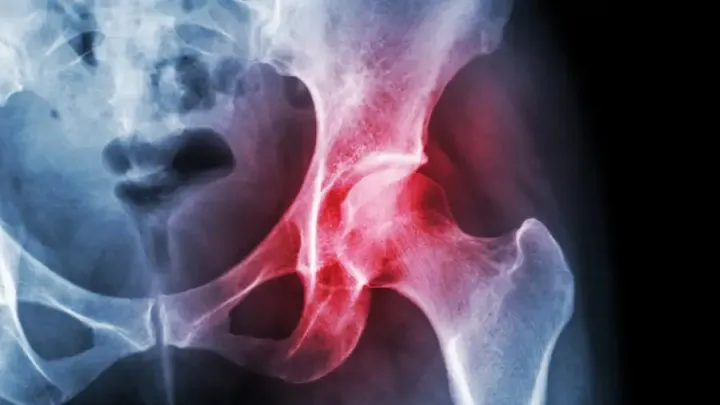

Разработаны особые наночастицы, облегчающие боль при остеоартрите

Препарат прошёл проверку на мышах.